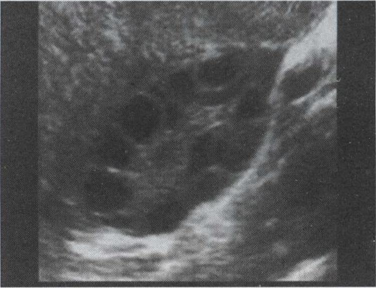

40.中年女性,中下腹横切面如图,箭头所示为